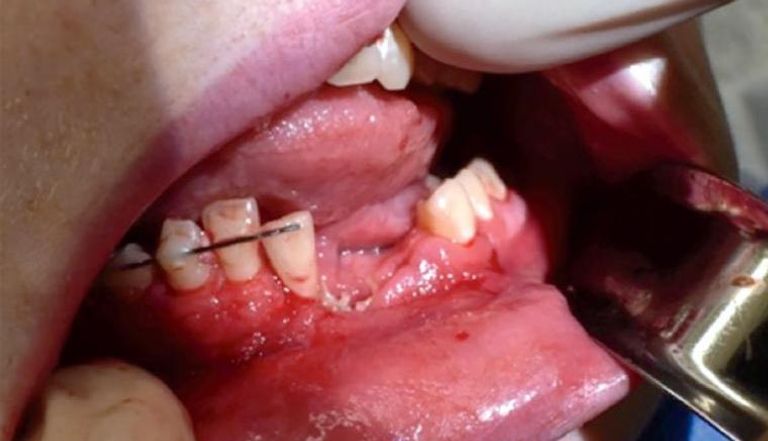

أصيب مراهق أمريكي بجروح خطيرة عندما انفجرت سيجارة إلكترونية في فمه وكسرت فكه، ما تطلب وضع صفيحة أسنان أسفل اللثة وتثبيتها في عظام الفك.

وقالت الدكتورة كاتي راسل، جراح الأطفال في جامعة يوتا ومستشفى الأطفال الابتدائي في سولت ليك سيتي، إن المريض أصيب بجروح شديدة في فمه وفقد بعض الأسنان، فضلا عن تكسر فكه الأسفل.

وأضافت: "الأطباء بحاجة إلى إزالة عدة أسنان أخرى من فم الصبي، لأن مآخذهم قد دُمرت، ويحتاج الفتى أيضا إلى وضع صفيحة أسنان أسفل اللثة لتثبيته في عظام الفك".

وما زال فك الصبي لا يغلق بشكل صحيح، لذا ربط الأطباء فكه لمدة 6 أسابيع لمنحه الوقت للشفاء.